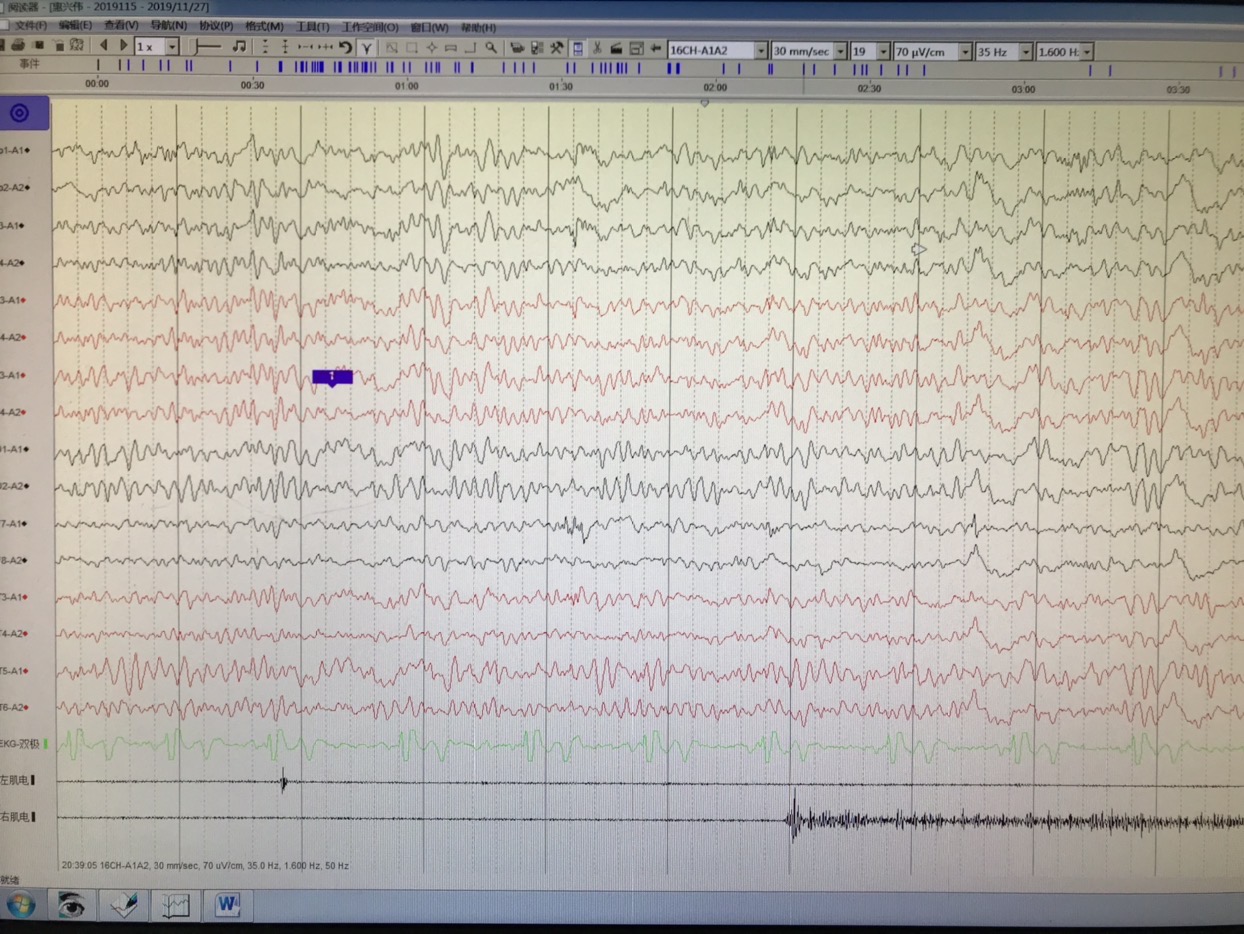

长程视频脑电监测提示左侧中央区、顶区、后颞区见中等量低-中-高波幅痫样放电。